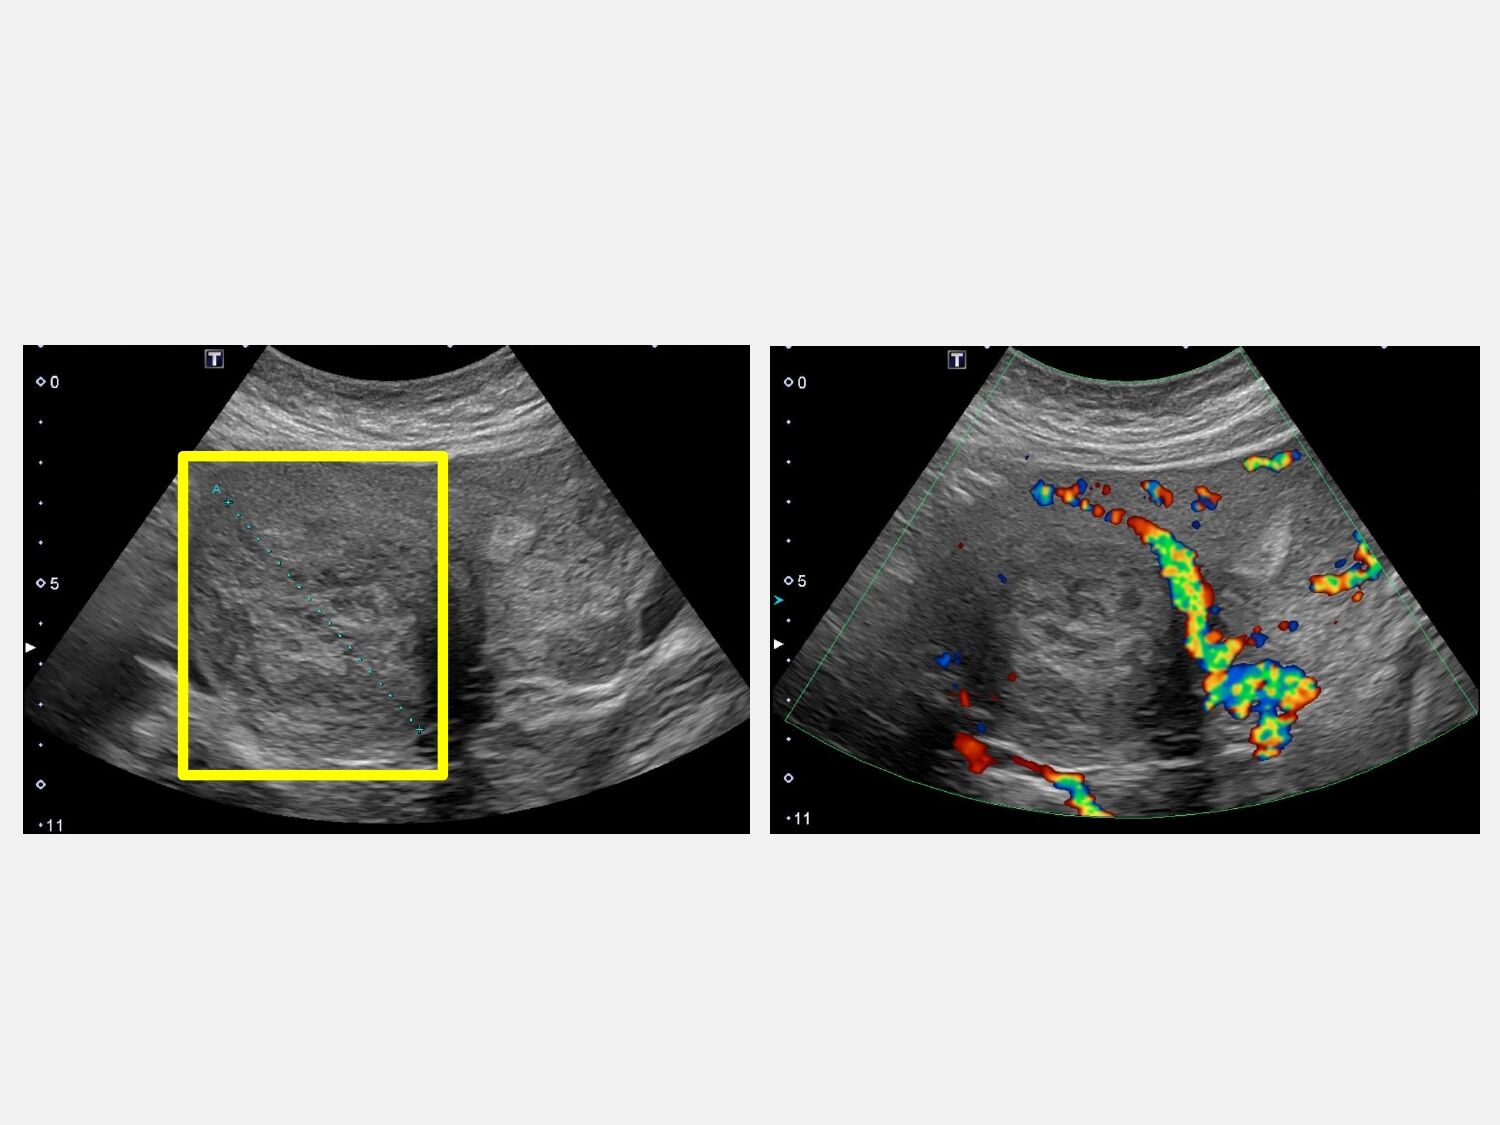

▲患者下腹有7公分肌瘤。(圖/大里仁愛醫院)

45歲的魏女士因為近半年下腹部悶痛,到仁愛長庚合作聯盟醫院(大里仁愛醫院)婦產科醫師林玉珊門診求診,檢查發現有下腹部悶痛合併壓迫症狀,竟然有7公分的肌瘤。經採用達文西機械手臂系統結合經陰道自然孔手術,患者術後一周即返家休養。由於手術並未在腹部留下傷口,讓魏女士感到非常驚訝,林玉珊表示,傷口藏在看不到的地方,這不只是手術傷口變小,更代表病人能更快回到自己的生活與角色中。